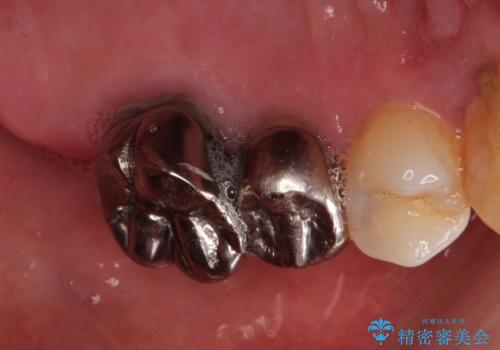

金属のかぶせ物をセラミックへ 根管治療からの再治療

左側の上下の奥歯に適合が悪く、レントゲン上でも根の治療が必要なところがありました。

再治療を行いました。

根管治療からの再治療を行ったことにより、治療期間が多少長くなりましたが、今後再治療の必要性があまりないような、精度の高い治療ができました。